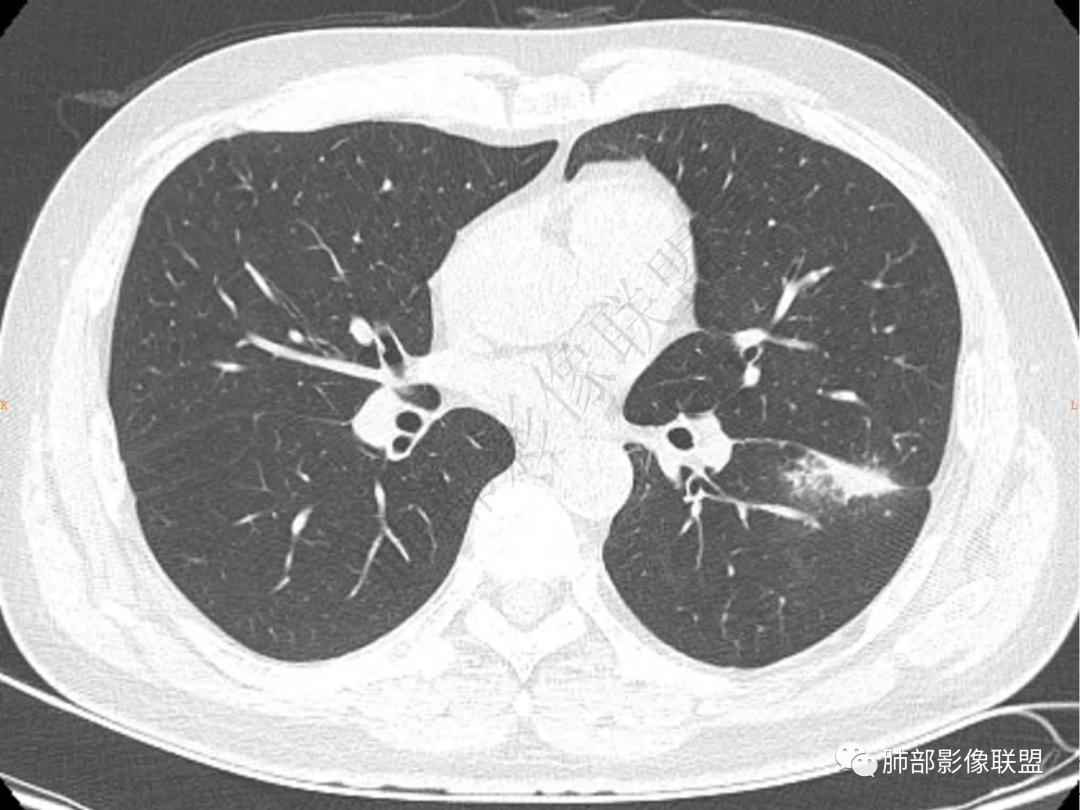

2.左肺下叶团片影,跨背段及内前基底段,实性部分类椭圆形,密度不甚均匀,可见毛刺及棘状突起,未见典型分叶及胸膜凹陷。病灶上下缘可见相应肺段支气管旁进侧出,管壁轻度增厚,未见狭窄阻塞。

3.周边较大范围磨玻璃影,边界相当模糊,小叶增厚明显。注意叶裂另一侧、左肺舌段亦可见磨玻璃影及增厚的小叶间隔。未见明确卫星病灶。

4.实性部分不均匀环形强化并显示一小范围低密度坏死区或空洞。较之肺窗,整体纵隔窗范围较小,提示病灶并不十分密实。抑或为不同时段图像。

一、与胸膜关系:

肺脓肿:可宽基底与胸膜相连,附近胸膜增厚——炎性特点

二、形态、边缘:

肺脓肿:边界模糊不清,或者块影为类圆形,无明显分叶,边缘平直为主,刀切征——炎性特点三、病灶周围特点:肺脓肿:病灶非远端有片状GGO——炎性特点四、近端支气管阻塞:肺脓肿:常有引流支气管伴管壁增厚或者支气管沿洞壁走行。五:坏死壁:肺脓肿:大多壁厚,少数壁薄,没有壁结节,内壁清楚光整——炎性特点